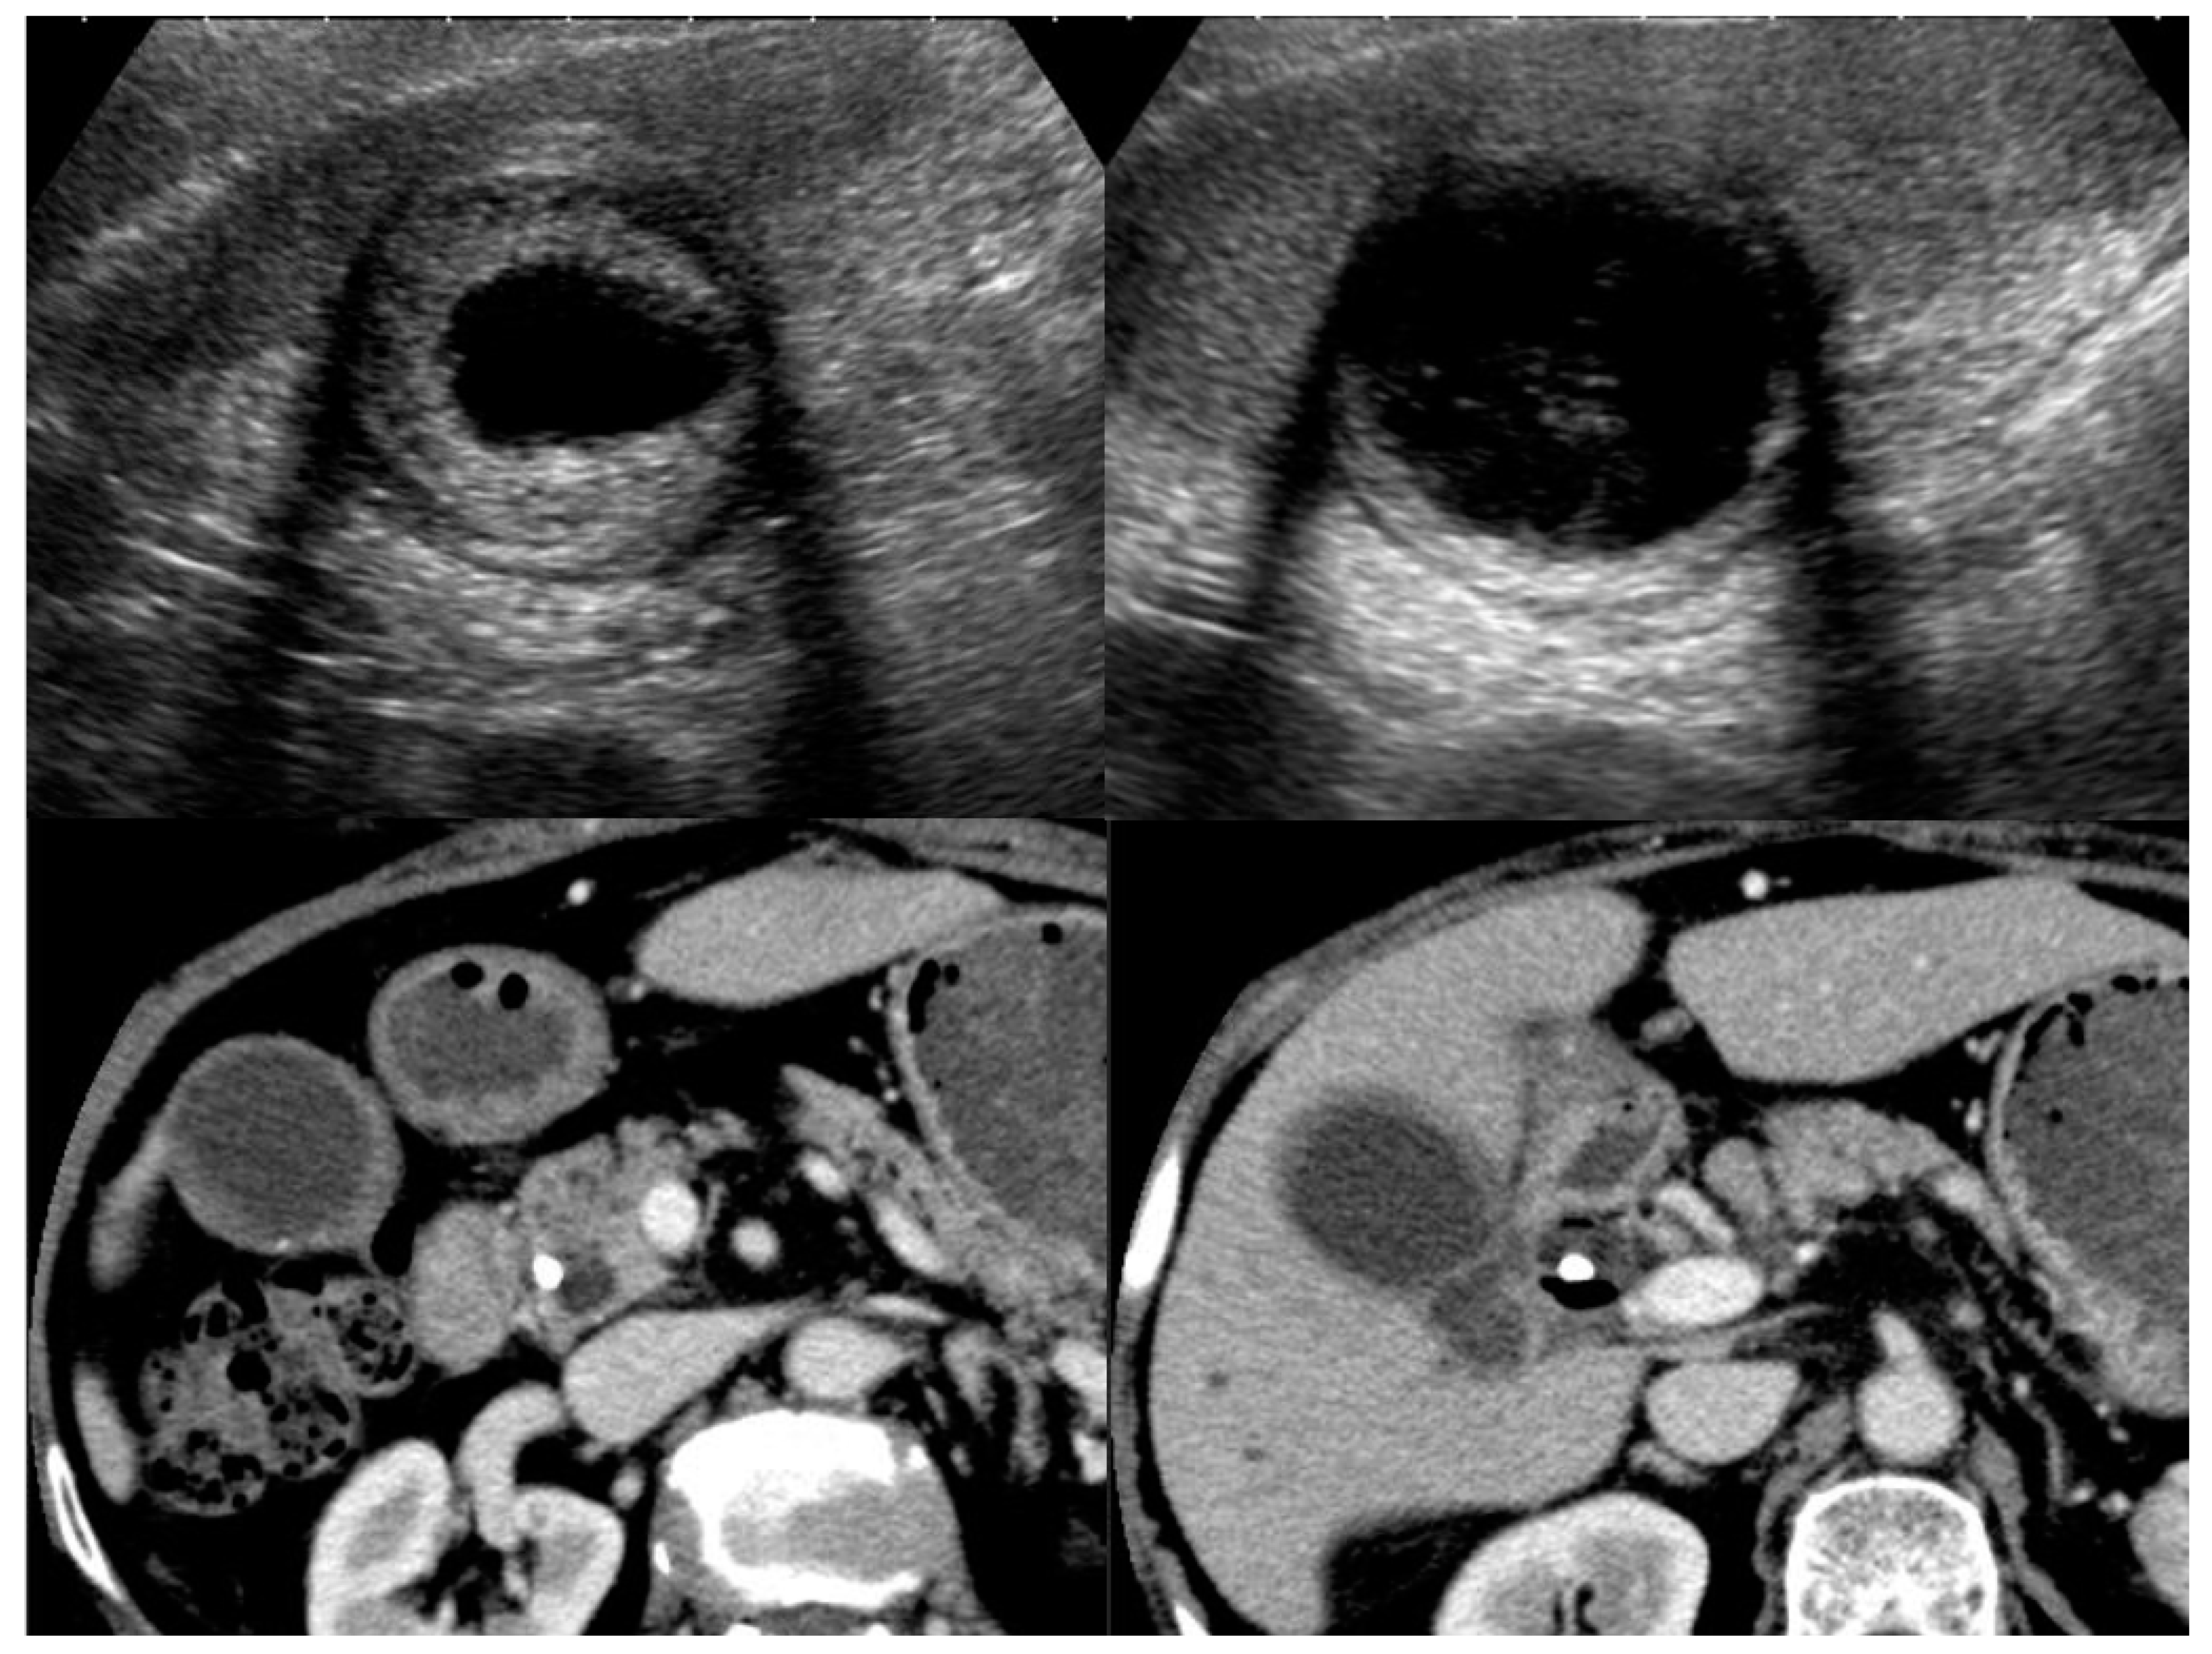

4.1. Diffuse Type of IgG4-CC

4.2. Localized Type of IgG4-CC

5.2. Adenomyomatosis